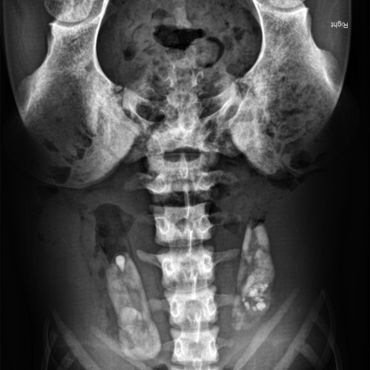

G: Okay. Hi, ich bin Gary. Ich bin eine Niere.

G: Ja. Ich habe mein ganzes Leben in einem anderen Körper verbracht. Dort wurde ich geboren. In diesem Körper lebe ich erst seit ein paar Monaten.

I: Ja, an sich sind neue Körperöffnungen eher kontraproduktiv fürs Überleben. Aber in deinem Fall – es klingt wie eine Transplantation – ist es doch eher gut.

G: Sicher, eine Lebendorganspende hört sich auf Anhieb gut an. Ist aber auch irgendwie Kidneynapping … Ich würde sagen, auf jeden Fall eine Form von Nierenraub.

G: Egal wie man es sieht: Ich befinde mich nun in diesem Körper, und mein alter Körper läuft irgendwo ohne mich herum.

G: O nein, nein, nein. Es ist völlig anders. Hier drin ist es absolut verrückt. Alles quetscht sich anders. Und der größte Unterschied? In meinem alten Körper … hatte ich Marco.

G: Marco. Meine andere Niere.

G: … hier gibt es nur mich. Und ich schätze, Marco ist nun auch allein. Er hat geschlafen, als ich rausgeholt wurde. Wir haben beide geschlafen. Er ist bestimmt ein paar Stunden später aufgewacht, hat rübergeschaut, und ich … war einfach weg. Keiner von uns wusste überhaupt, dass wir gehen konnten. Wir dachten, unser Körper sei das ganze Universum. Ich schätze, Marco tut das immer noch, und ich bin einfach nicht mehr da. Am liebsten würde ich weinen. Aber ich kann nur Blut und Urin machen.